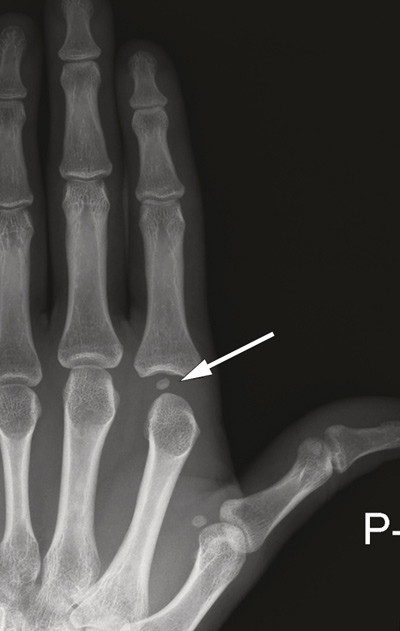

Den volare platen, en bindevevsplate som forsterker leddkapselen, bidrar til volar stabilitet ved metakarpofalangealleddet. Hos de fleste er det i enkelte av disse leddene «innebygd» sesambein i volarplaten. I en studie basert på røntgenbilder av 442 personer fra middelhavsland hadde 99,5 % sesambein ved første metakarpofalangealledd, nest vanligst var det ved annet metakarpofalangealledd (42,3 %), dernest ved femte (41,1 %) (2). Røntgenbildene av pasientens hånd viste et sesambein i leddspalten (pil), et patognomonisk tegn på at volarplaten, som sesambeinet er festet i, er rumpert og ligger låst mellom leddflatene. I slike tilfeller lukserer i tillegg caput metacarpale palmart og blir låst mellom sener, muskler og ligamenter. Dette er en kompleks luksasjon, som forekommer forholdsvis sjelden.